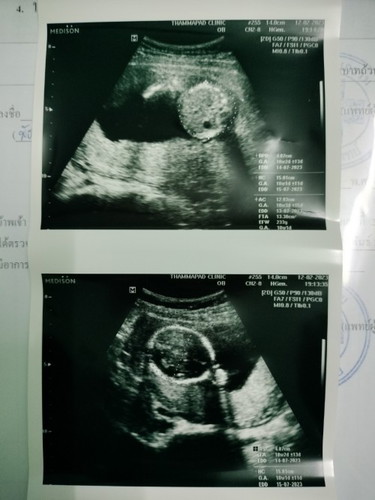

คุณแม่บ้านไหนทีมคลอดกรกฎาคม รู้เพศแล้วบ้างคะ บ้านนี้ได้ลูกสาวจ้า 18+3 วิค

เมื่อวานไปซาวด์คุณหมอบอกได้ลูกสาวค่ะ แม่กลัวลูกแอบมาก👧🏻 ได้ลูกสาวจริงๆไช่มั้ยคะ #ลูกคนแรกค่ะ